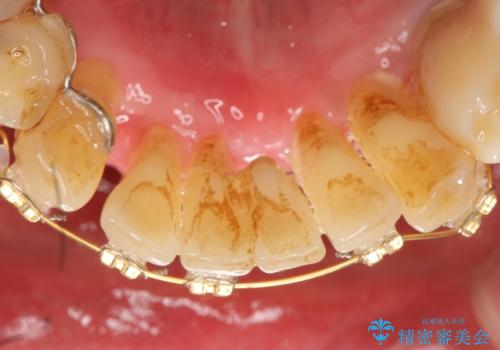

- 歯がぐらぐらで咬めないことを主訴に来院された患者様です。

仕事が忙しくなかなか自分のことに気が回らなかったそうですが、どんどん歯の動揺が増し「もう限界だ!」と思い受診を決断したとのことでした。

精査したところ、全顎的な重度の歯周病により下顎前歯に激しい動揺を認めました。

歯も神経も残したいという患者様のご希望により、補綴前に部分矯正を行っております。

補綴前に部分矯正を行うことで、歯の神経も保存することができました。